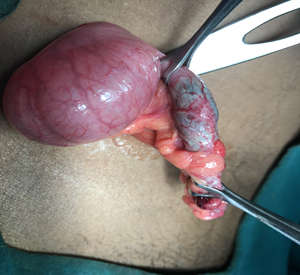

At Remedy Hospital we offer surgery for all conditions of appendix like appendicitis, appendicular malignancy, and mucocele of appendix. We offer surgery by latest technique (Laparoscopic Appendectomy) as well as time tasted conventional technique (Open Appendectomy).